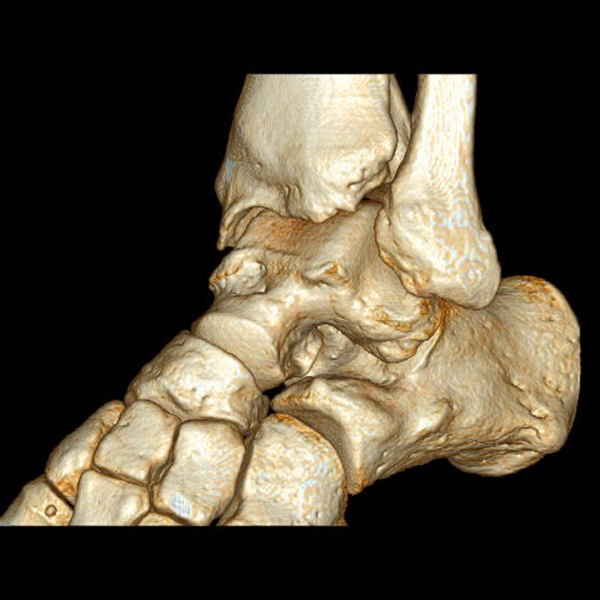

Der Computertomographie (CT) fehlt ebenfalls die Fähigkeit, den Knorpel direkt zu bewerten. Mit dem CT können jedoch weitere Details der knöchernen Verletzung, wie Größe, Form, Umfang und evtl. Dislokation der Läsion beurteilt werden 11. Insbesondere kleine Knochenkanten oder Gelenkkörper lassen sich in der CT wesentlich besser darstellen als mit einem MRT.